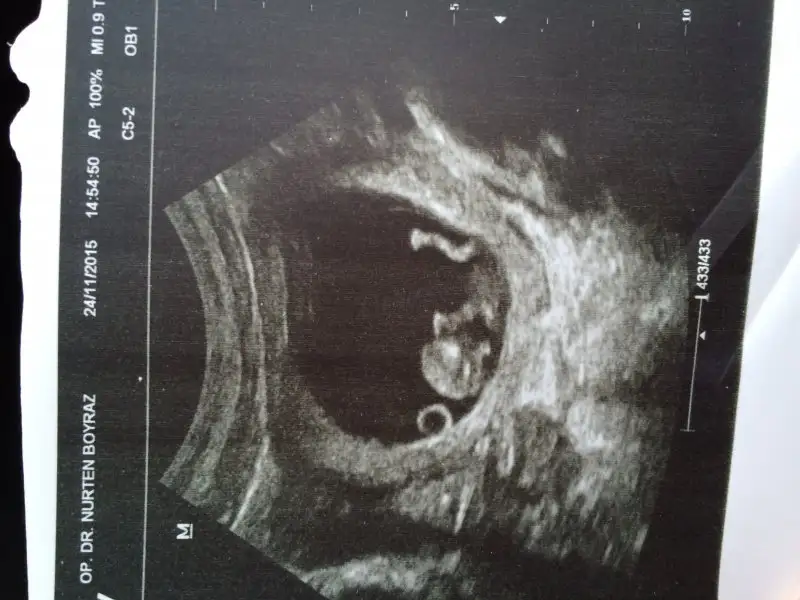

Avrupa safak hastanesi gaziosmanpasa. Canim ense ölçümü yapıldı 1,45 mm cikti doktor çok iyi dedi kan verdim 2 li icin oda guzel çıktı cok sukur